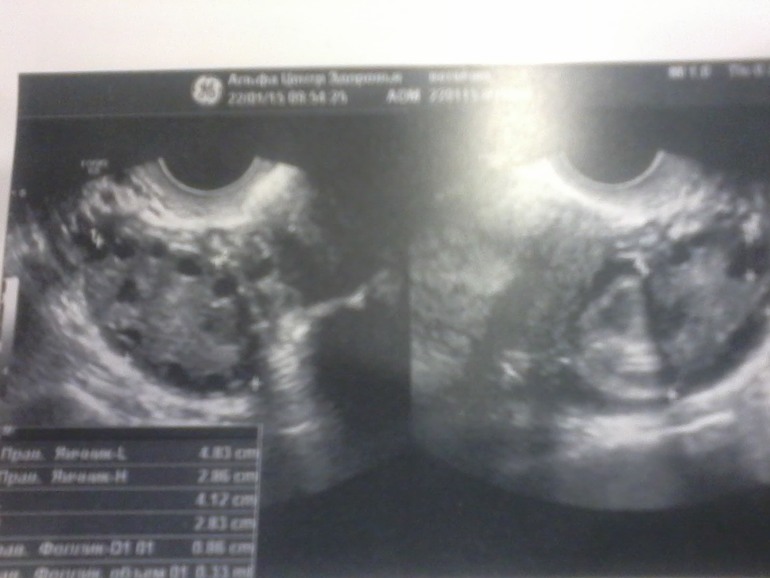

Правый яичник, размеры: 48*29*20мм, объем 14 см.куб, обычной фолликулярной структуры с антральными фолликулами до 4-6 мм. С крупным фолликулом до 9мм.

Левый яичник, размеры 41*28*18мм, объем 11 см.куб., обычной фолликулярной структуры с антральными фолликулами до 4-6 мм., С крупным фолликулом до 11 мм.

Заключение:Увеличение объема яичников